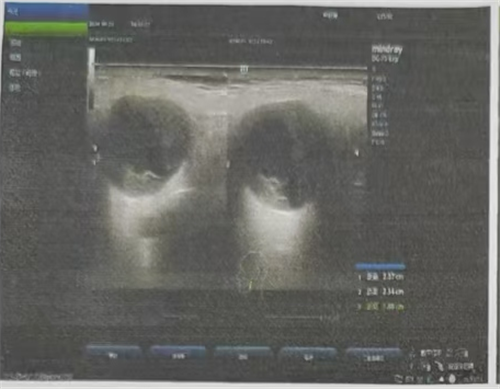

目前腮腺区肿瘤手术方式多为腮腺肿物切除 + 腮腺腺叶切除 + 面神经解剖(若术后病理提示恶性肿瘤,需联合放化疗)。术前需完善腮腺区彩超及颌面部影像学检查,必要时加做颌面部增强 MRI 检查,以明确病变范围、肿物大小、性质以及与周围组织解剖学关系。